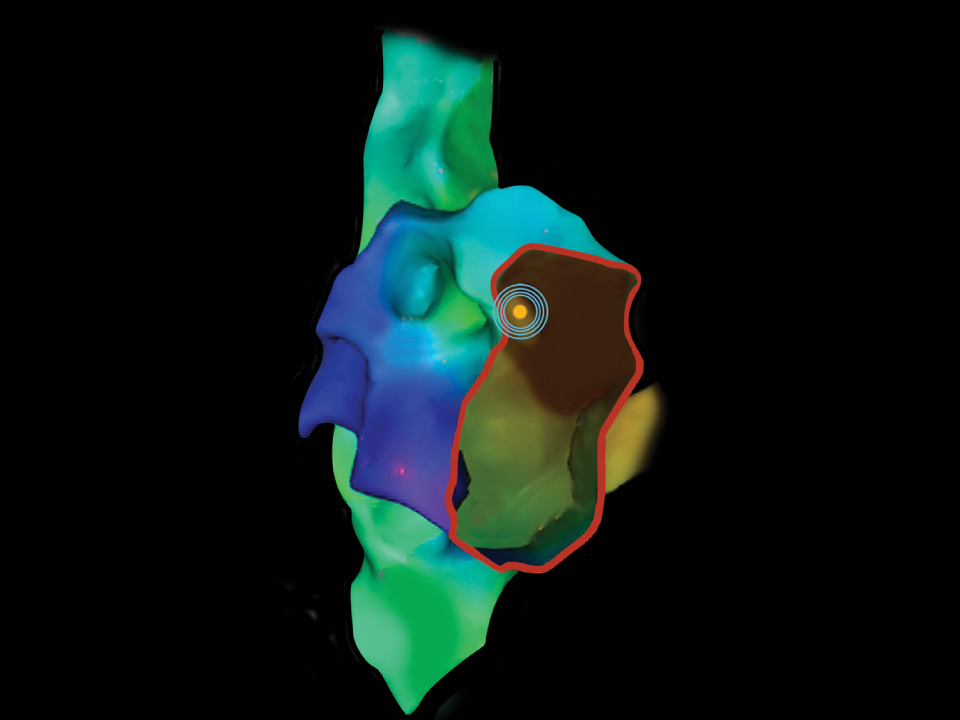

Mapping system showing location of VersaCross RF Wire tip.

Mapping

Track and mark RF wire tip position on your mapping system